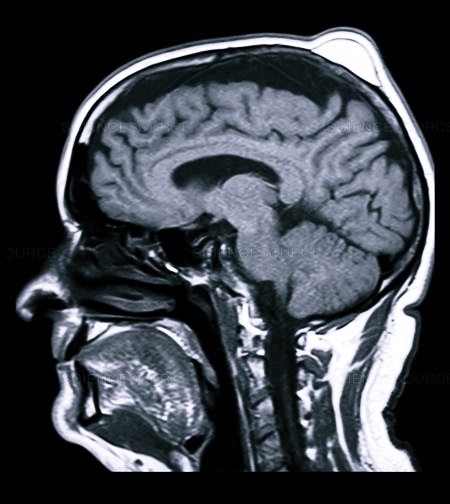

На голове проводится и УЗИ исследование, помогающее определить видоизменения в тканях и костных структурах, иногда МРТ, в виде дополнительной меры диагностики.

- Рентгенография позволяет выявить образования костной плотности (остеома) или обнаружить причину воспаления лимфоузла (ринит, синусит, хронический периодонтит).

- УЗИ дает возможность определить изменения в структуре мягких тканей, наличие размягчения или жидкостного компонента, а также степень изменения структуры лимфоузла при его воспалении.

Первичный диагноз выставляется на основании внешнего осмотра, жалоб больного, данных анамнеза. Для его подтверждения иногда требуется проведение ряда инструментальных исследований:

- рентгенографии;

- МРТ или КТ;

- ангиографии;

- ультразвукового исследования.